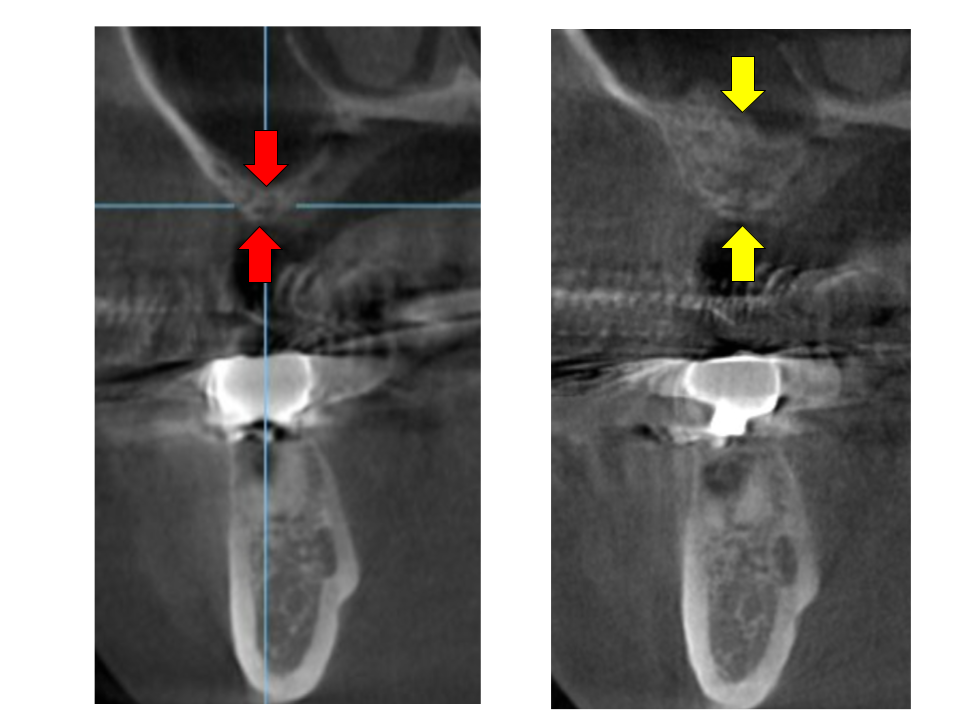

インプラント周囲炎のレントゲン

インプラント周囲の清掃が不十分な状態が続くと、天然歯における歯周炎(歯槽膿漏)と同様に、インプラント周囲組織に炎症が生じることがあります。

インプラント周囲に炎症が起こると、生体はインプラントを異物として認識し、排除しようとする防御反応が働きます。その結果、周囲の骨組織が吸収され、インプラントの支持が失われてしまうことがあります。